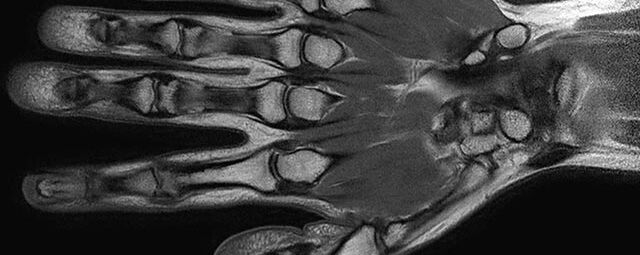

Gelenke

Hand

• Beurteilung von Knochen, Bändern und anderen Weichteilstrukturen der Gelenke nach Unfall.

• Arthrosediagnostik (Knorpelschaden)

• Impingement-Symptomatik

• Ursachenklärung bei wiederholter spontaner Gelenkluxation

• Ausbreitungsdiagnostik bei Gelenkentzündung, z.B. im Rahmen von rheumatischen Grunderkrankungen

Arthrographie

• MR-Arthrographie – nach örtlicher Betäubung und gründlicher Desinfektion der Haut wird unter Lagekontrolle mit Röntgen-Durchleuchtung eine kleine Nadel in den Gelenkraum positoniert und darüber ein MR-taugliches Kontrastmittel in den Gelenkraum gespritzt. Danach wird die Nadel entfernt. Anschließend erfolgt die MRT des Gelenkes. Diese Methode stellt kleine anatomische Strukturen des Gelenkraumes verbessert dar, z.B. zur Therapieplanung vor Arthroskopie bei Sportverletzungen der Schulter oder Gelenkinstabilität.